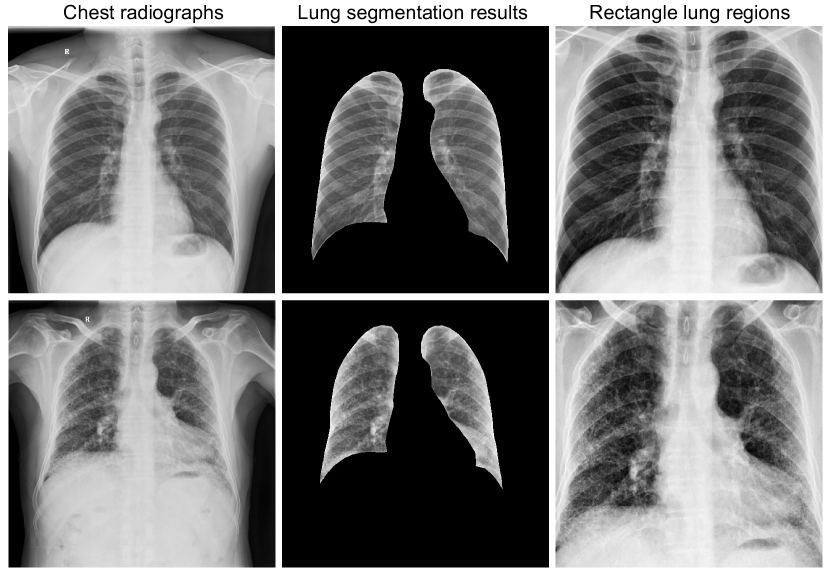

Fig. 5: The illustration examples of dataset preprocessing: two examples labeled as ”Pneumoconiosis” and ”Normal”. The segmentation results are obtained using the CheXmask pipeline, as proposed in the paper by Gaggion et al.[13]. The selection of the rectangular lung regions is based on the largest external rectangle of the segmentation results.

In the preprocessing phase, all chest radiographs are initially processed using the pyplot.imsave function to automatically adjust the contrast and brightness of the DICOM format (UInt16) pixel array, converting it to UInt8 PNG format. Next, we employ the CheXmask pipeline, introduced by Gaggion et al. [13], for lung segmentation. Based on the lung segmentation results, we use the maximum external rectangle extraction technique to isolate the rectangular lung regions in original chest radiographs. Finally, we resize them into a uniform size of 224×\times224 pixels for analyses. Fig. 5 displays representative chest radiographs, showcasing both categories, their corresponding lung segmentation results, and the extracted rectangular lung regions.